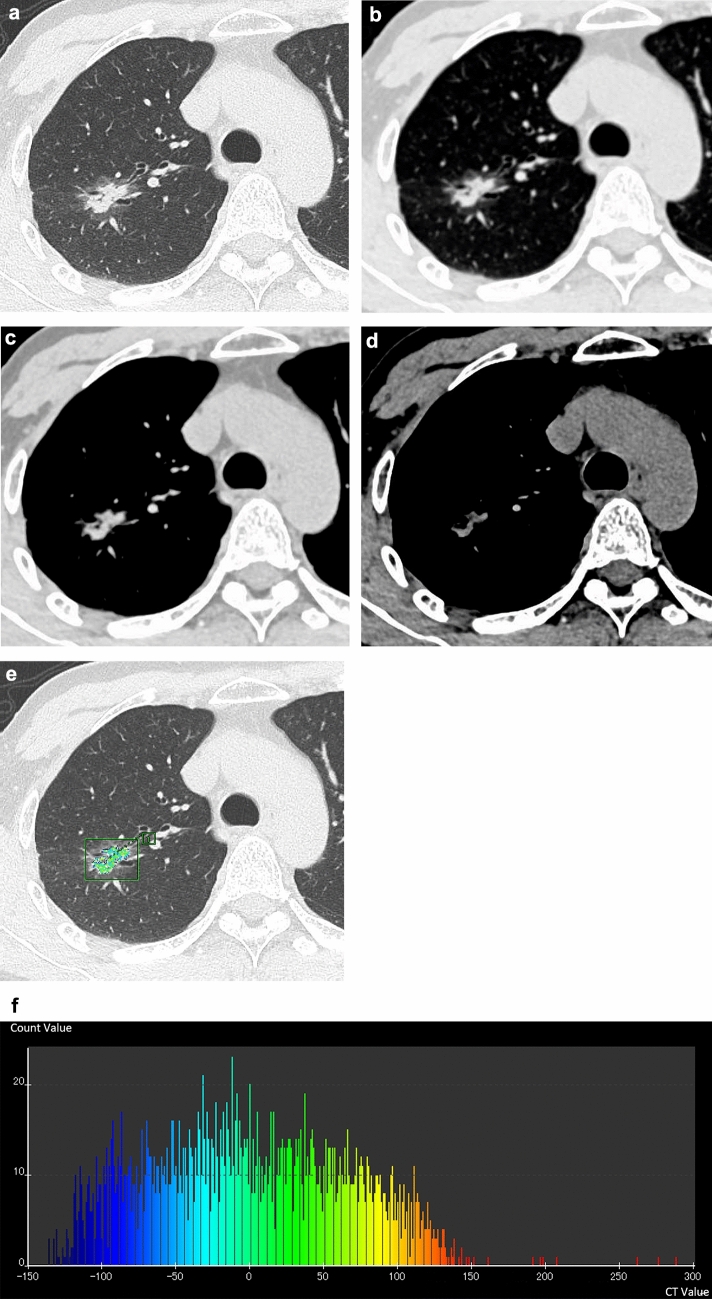

Materials and methods: A total of 54 cases were included in this study. The diagnoses of lung adenocarcinoma consisted of AIS or MIA (n = 20) and IAC (n = 34). The following factors were evaluated on CT images: part-solid nodule or solid nodule, presence of air bronchogram, air space, calcification within the tumor, presence of interstitial pneumonia and emphysema, diameters of the tumor and solid component, and CT values of the solid component. The volume and CT number histograms, including the 50th, 75th, and 100th percentiles of solid component were obtained using a software program. The CT criteria were compared between AIS, MIA, and IAC, and an indicator of differentiation was considered.

Results: Part-solid nodules were observed more frequently in AIS and MIA (85.0%) than in IAC (55.9%). All criteria for quantitative analysis showed significant differences between AIS or MIA and IAC, and the diameter of the solid component in the mediastinal window was an indicator of differentiation (p = 0.0006; odds ratio, 1.4; 95% confidence interval, 1.2-1.8).

Conclusion: The diameter of the solid component on the mediastinal window was considered an indicator of differentiation between AIS, MIA, and IAC.

Condensed abstract: Quantitative data of solid component, including both manual measurements and evaluation using CT software, are correlated with pathological invasiveness. Diameter of the solid component in the mediastinal window would be an indicator of IAC.